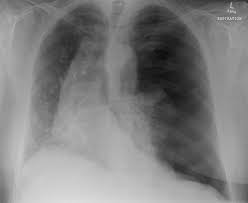

Pneumothorax High Res Stock Images Shutterstock from image.shutterstock.com Aug 11, 2021 · fenton 2013 growth calculator for preterm infants. The degree of collapse determines the clinical presentation of pneumothorax. Search only for pneumothorax x ray This buildup of air puts pressure on the lung, so it cannot expand Now with integrated gestational age calculator and decision support (e.g., retinopathy of prematurity, rsv prophylaxis). Jul 02, 2021 · a collapsed lung occurs when air escapes from the lung. Nov 16, 2020 · a pneumothorax is defined as a collection of air outside the lung but within the pleural cavity. Air can enter the pleural space by two mechanisms, either.

Chest X Ray Showing Large Right Pneumothorax With Collapsed Lung Download Scientific Diagram from www.researchgate.net Jul 02, 2021 · a collapsed lung occurs when air escapes from the lung. Air can enter the pleural space by two mechanisms, either. Now with integrated gestational age calculator and decision support (e.g., retinopathy of prematurity, rsv prophylaxis). Search only for pneumothorax x ray It occurs when air accumulates between the parietal and visceral pleurae inside the chest. The air accumulation can apply pressure on the lung and make it collapse. The degree of collapse determines the clinical presentation of pneumothorax. This buildup of air puts pressure on the lung, so it cannot expand